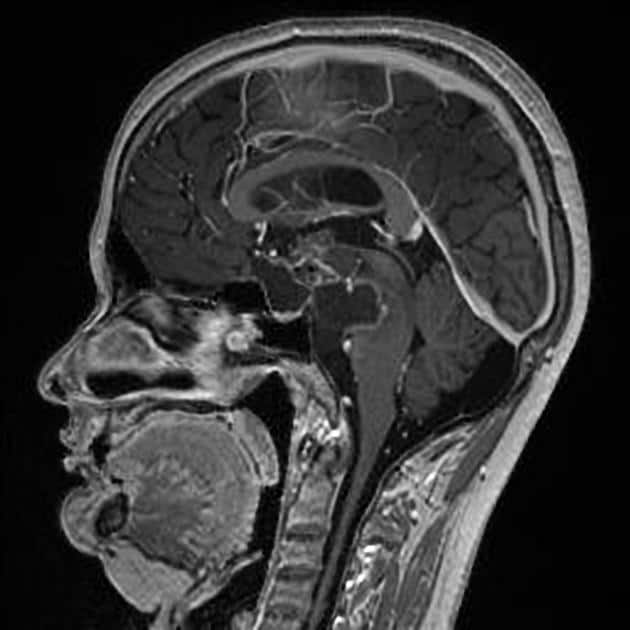

U sọ hầu

» Thông tin: Nam giới – 30 tuổi.

» Lâm sàng: Đau đầu.